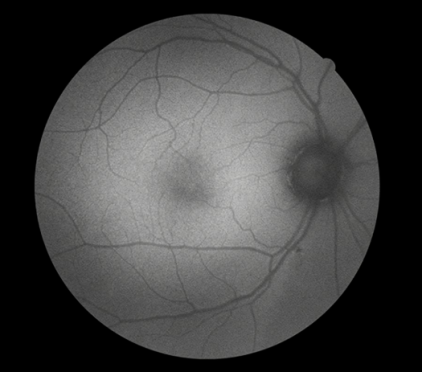

FFA是20世紀(jì)60年代發(fā)展的一項(xiàng)技術(shù)。1961年Navotny 和Alvis首次成功地用膠片記錄到熒光素流經(jīng)視網(wǎng)膜和脈絡(luò)膜血管的動(dòng)態(tài)過程,開創(chuàng)了眼底熒光血管造影的臨床應(yīng)用時(shí)代。如今,F(xiàn)FA主要用于觀察視網(wǎng)膜血管及其血液循環(huán)狀態(tài),高清晰攝像技術(shù)能動(dòng)態(tài)捕捉視網(wǎng)膜毛細(xì)血管的循環(huán)狀態(tài),間斷或連續(xù)采集可形成視網(wǎng)膜靜態(tài)的黑白圖像或動(dòng)態(tài)圖像,在診斷中敏感性強(qiáng),確診率高,能發(fā)現(xiàn)檢眼鏡或眼底照相下不易發(fā)現(xiàn)的視網(wǎng)膜深層微血管瘤,是判斷視網(wǎng)膜病變的“金標(biāo)準(zhǔn)”。

FFA影像